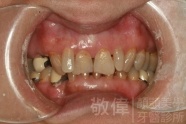

| 6 | 前牙美容 | 矯正+牙齦增補+晶鑽全瓷冠 | ||

| 7 | 前牙美容 | 矯正+晶鑽全瓷冠 | ||